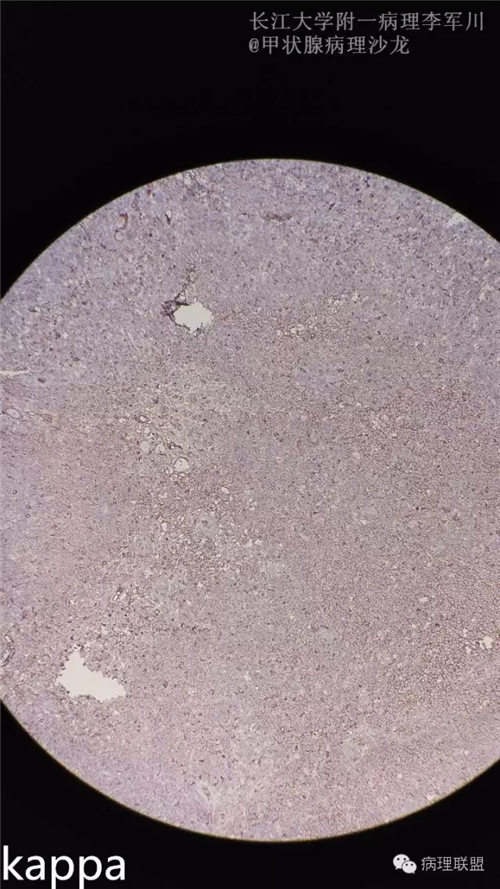

甲状腺病变中的MALT?

女,40余岁,右侧甲状腺肿块,直径约3cm。

病例由长江大学附一病理李军川提供,致谢。